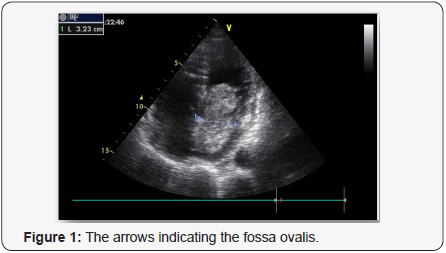

A 79-year-old woman was admitted to our hospital because of a syncopal episode followed by altered mental status. The patient was at her usual state of health with a six-month history of exertional dyspnea managed as bronchial asthma, when she suddenly lost consciousness and vomited while walking. She was transferred by ambulance to the emergency department within 40 minutes after the onset of symptoms. On arrival, she said she did not have chest pain or headache, but she was unable to provide other history. On examination, she was lethargic, with periods of unresponsiveness. There was no sign of head trauma; the remainder of the examination was normal. A radiograph of the chest showed pulmonary vascular prominence with no evidence of edema, infiltrate or effusion. An electrocardiogram revealed sinus tachycardia with ST – segment elevation in V3 through V6. Tests for creatinine kinase and troponin T were negative. Transthoracic echocardiography showed hypokinesis of the anterior, septal, and apical walls of the left ventricle. Overall left ventricle systolic function was at the lower limit of the normal range. The left atrium was dilated. There was a large pedunculated mobile echodensity in the left atrium that was attached to the atrial septum (Figures 1 & 2).The mass was obstructing flow with a mean trans mitral gradient of 17mm Hg, with a reduced stroke volume and moderate to severe pulmonary hypertension with an estimated right ventricular systolic pressure of 90 mm Hg. Subsequent transesophageal views revealed a mass 7cm x 3cm x 3.4cm with its base attached to the interatrial septum. The mass was highly mobile with multiple frondlike elements. Color Doppler imaging showed no evidence of a patent foramen ovale. Magnetic resonance imaging (MRI) of the brain revealed no new infarcts. An emergency Interventional angiography performed prior surgical excision and approximately 12 hours after the onset of symptoms revealed an occlusive filling defect in the proximal portion of the circumflexus coronary artery. Balloon dilatation and DES implantation improved filling. The patient was intubated, a nasogastric tube was placed and moved to the operating room. Subsequently, surgical resection of the left atrial mass was performed via transatrial surgical approach and the atrial septum defect repaired with a homologue patch. The resected mass was 7cm x 3cm x 3.4cm, with an irregular frondlike surface (Figures 3 & 4). On microscopical examination, the mass also had the morphologic features of a cardiac myxoma.

The majority of myxomas are solitary and occur in the left atrium, typically in the zone of the fossa ovalis [12], as in this case. It can be seen in patients between 3-83 years old, with the majority presenting in fifth decade of life and just few cases are mentioned presenting left atrial myxoma after the seventh decade. Is most commonly seen in women with 90% being solitary and pedunculated and 10% being familial, with an autosomal dominant pattern of inheritance [13] When multiple, recurrent, ventricular or familial myxomas are discovered, there is cause to consider the diagnosis of Carney’s syndrome, a familial syndrome characterized by multiple neoplasms [14]. The clinical features of atrial myxoma vary, as well as the size, with most cases in literature referring to myxomas sized between 0.4 to 6,5 cm[15]. Large tumors are related to atrial fibrillation.

Echocardiography was reported to be the definitive diagnostic modality. The sensitivity of transthoracic echocardiography is about 95% determine accurately the location, the size, the attachment and the mobility of the mass. Transesophageal echocardiography has nearly 100% sensitivity for cardiac myxoma. The tumor tissue manifests as spherical – pedunculated mass attached to the endocardial surface with hypoechoic areas [25].